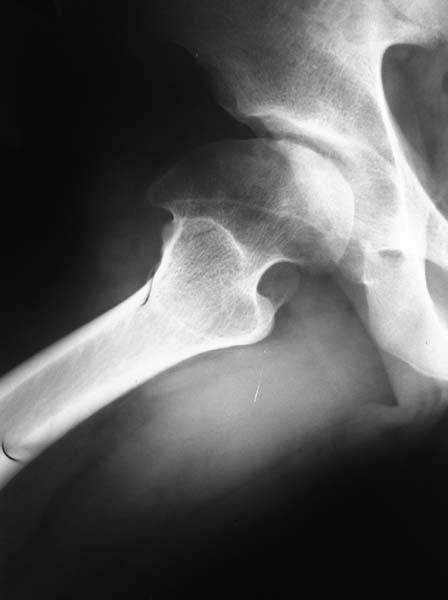

Снимок выполнен в прямой проекции с внутренней ротацией. На днях сделаем СКТ с 3D модуляцией.